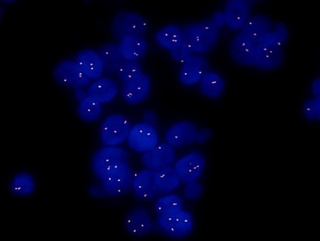

明美熒光顯微鏡應(yīng)用于腫瘤輔助診斷研究

深圳某科研檢測公司需要開展對(duì)腫瘤的輔助診斷研究,需要用到熒光原位雜交技術(shù)(Fluorescence In Situ Hybridization, FISH). Mshot明美推薦了研究級(jí)熒光顯微鏡MF43-N搭配四通道光源MG-120,可以即開即用提供高質(zhì)量的熒光和明場成像,可以自主選擇和升級(jí)熒光激發(fā)塊,可對(duì)FISH樣品進(jìn)行單色熒光或雙色熒光觀察。搭配明美自主研發(fā)的FISH熒光原位雜交分析軟件,快速成像,自動(dòng)著色,一鍵合成多色熒光圖像,直觀地判斷最終的實(shí)驗(yàn)結(jié)果,功能強(qiáng)大,使用方便,效果得到客戶認(rèn)可。